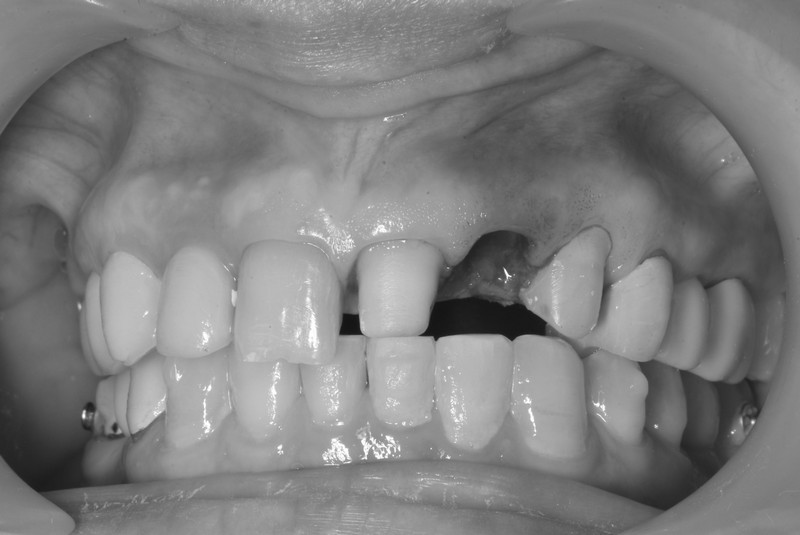

立即式植牙(即拔即種)

拔除牙齒的時候同時植入人工牙根,減少手術次數與等待時間,快速恢復咀嚼與外觀,縮短療程並降低不適感,適合即將拔除壞牙需植牙之患者。